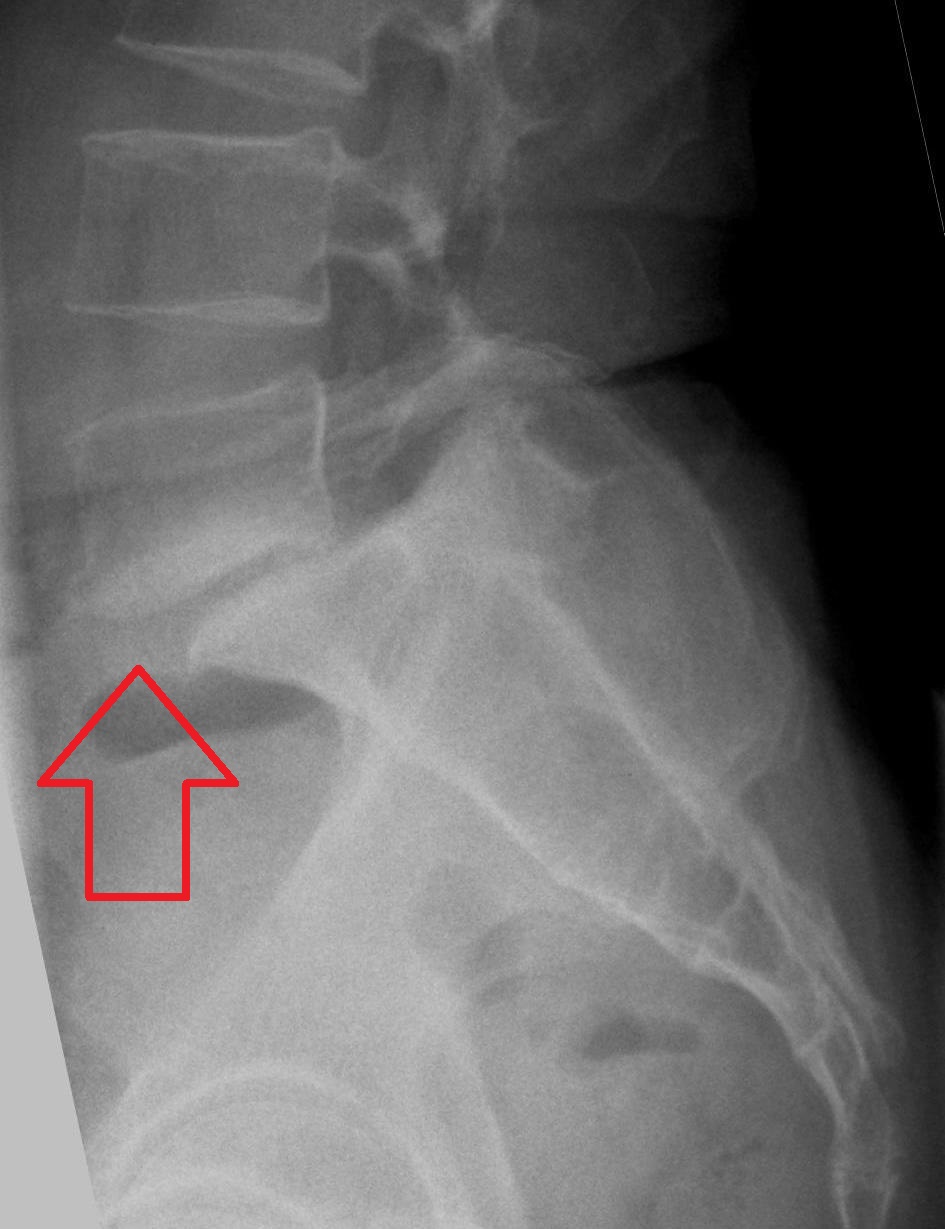

compression fx

collapse of body from osteoporosis, kyphosis, trauma, or pathologic disease. Anterior wedge collapses, changing the shape to a wedge, best demoed on a lateral spine